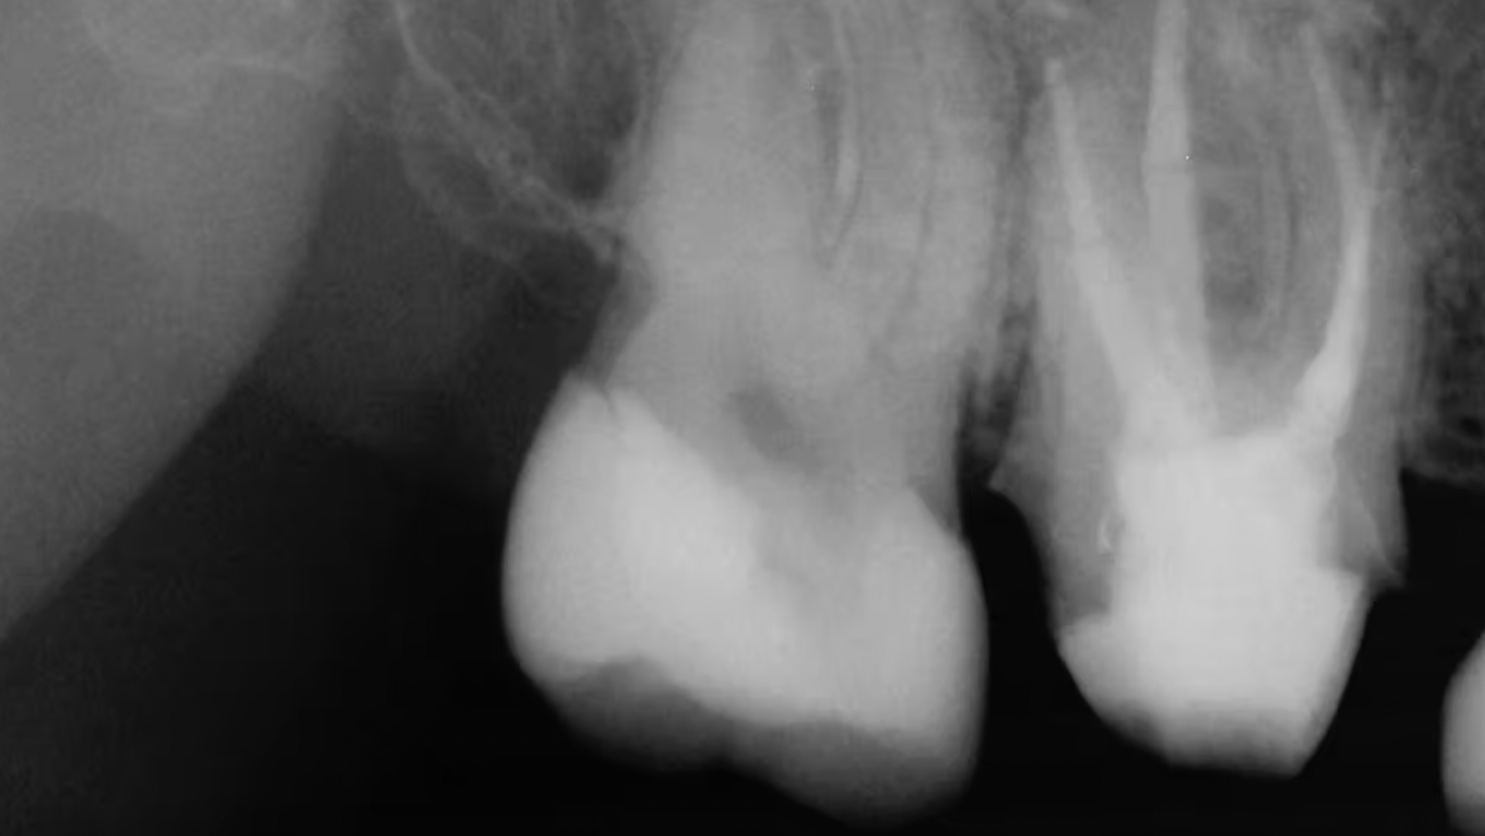

No tooth structure remaining coronal to the gingival tissue

There are clinical situations in which these teeth should be retained, including if the practitioner plans to extrude the tooth orthodontically. However, when considering the clinical success of dental root-form implants compared to questionable teeth, it is often better to extract the teeth and place implants. In the debatable event that a decision is made to restore such teeth, a post in single-rooted teeth or more than one post in multirooted teeth should be placed. Even with adequately placed posts present, the long-term success of such teeth is very questionable.